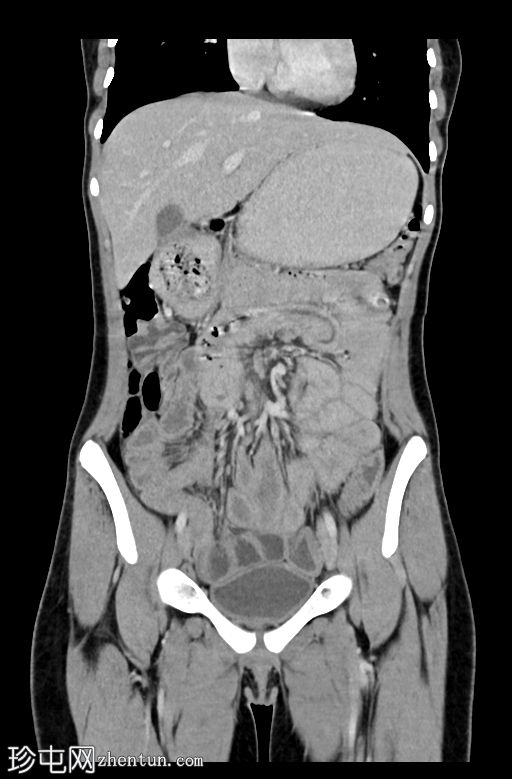

冠状C+门静脉期

小肠中央可见曲线/管状充盈缺损,因运动而略微模糊。小肠轻度增厚。其他检查正常。

地方性人群中小负担蛔虫病的典型表现,小肠轻度(相对轻微,甚至可能不明显)增厚,小肠中央可见特征性的管状曲线充盈缺损。